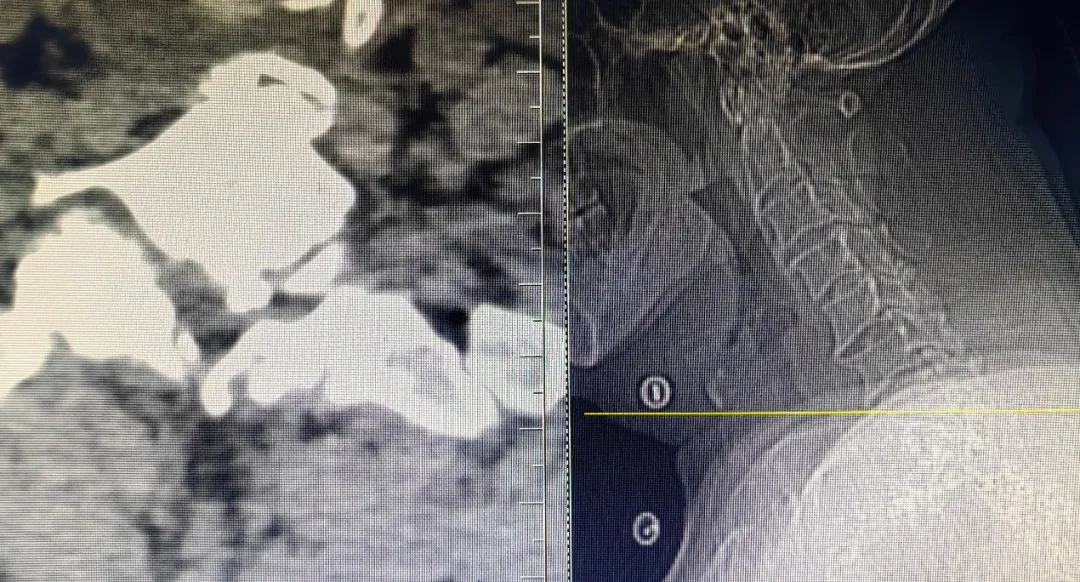

上图为术后复查CT

可见神经根管较术前变宽